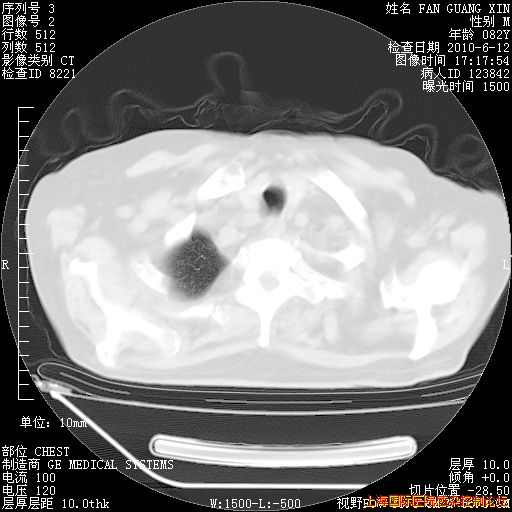

补发6月12日肺部CT肺窗

6月12日肺窗

6月12日纵膈窗